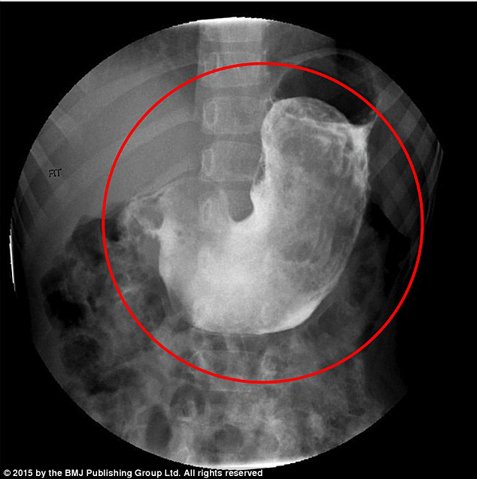

Μάζα βάρους 125 γραμμαρίων, που είχε το μέγεθος ενός μήλου, αφαιρέθηκε με χειρουργική επέμβαση σε πεντάχρονο κορίτσι στην Αδελαΐδα της Αυστραλίας. Το κορίτσι, αφού μεταφέρθηκε σε νοσοκομείο με πόνους στην κοιλιά, διαπιστώθηκε ότι έπασχε από τριχοτιλλομανία, μια κατάσταση κατά την οποία το άτομο τραβά τις τρίχες από τα μαλλιά του, και τριχοφαγία, κατά την οποία τις καταναλώνει. Σύμφωνα με δημοσίευμα της «Daily Mail» η μικρή τις τελευταίες μέρες είχε εμφανίσει μειωμένη όρεξη και ενοχλήσεις στο στομάχι. Οι γιατροί χαρακτήρισαν την κατάσταση του κοριτσιού «Σύνδρομο της Ραπουνζέλ».

Η μικρή ανέφερε ότι είχε παρατηρήσει τρίχες στα κόπρανά της και σε εμετό που είχε κάνει στο παρελθόν. Ύστερα απο ιατρικές εξετάσεις και ακτινογραφίες, διαπιστώθηκε η ύπαρξη μιας μεγάλης, συμπαγούς, μαλακής μάζας στο στομάχι της που δημιουργήθηκε από τις τρίχες που είχε καταπιεί. Επιπλέον, οι εξετάσεις έδειξαν εκτεταμένες κακώσεις στο στομάχι της και μικρότερες στο έντερο. Η μικρή βρίσκεται σε στάδιο ανάρωσης και συμπεριφορικής θεραπείας για να ξεπεράσει το σύνδρομο.